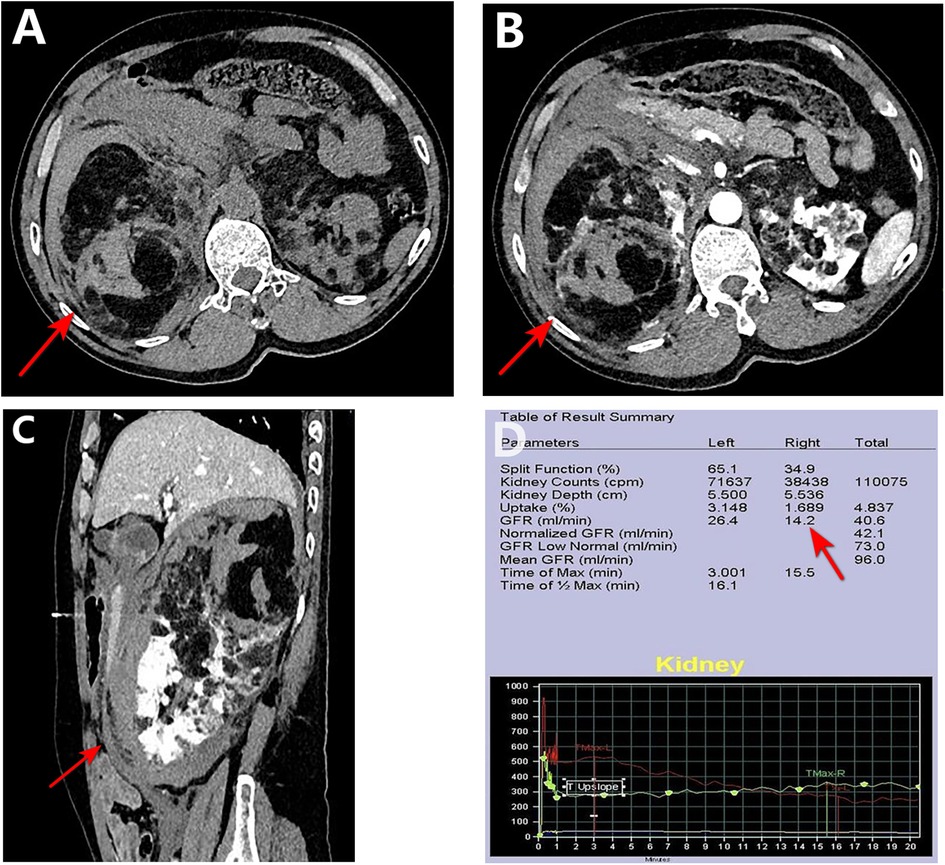

The patient was a 59-year-old man who was admitted to the emergency room with “right upper abdominal distension and pain for 4 h”. He denied any history of epileptic seizures and his personal, familial, or marital history were unremarkable, and his intelligence was normal. His temperature, heart rate, respiratory rate, blood pressure, oxygen saturation, and body mass index were 36.7°C, 81 beats/min, 23 breaths/min, 155/89 mmHg (1 mmHg = 0.133 kPa), 98%, and 23.4 kg/m2, respectively. The skin at the bilateral nasolabial folds showed a butterfly-shaped distribution of dark red papules; around the mouth, nose, and lower lip, we observed a dark red papule with a size ranging from a grain of rice to a green bean, exhibiting a hard texture. The nails of both toes were rough and thick, and a mung bean-sized fibroma was observed on the nail bed of the bunion of each lower limb (Figure 1). Abdominal examination: palpable mass in the right abdomen, slightly hard, right abdominal muscle tension, obvious pressure pain, no obvious rebound pain, and positive percussion pain in the right kidney area. Laboratory results on admission were as follows: white blood cell count, red blood cell count, platelet count, hemoglobin level, and blood creatinine of 7.61 × 109/L, 3.12 × 1012/L, 56 × 109/L, 95 g/L, and 72.7 umol/L, respectively. The results of liver and kidney function, electrolyte levels, coagulation, and urinalysis were within normal limits. Enhanced abdominal computed tomography (CT) showed multiple vascular smooth muscle lipomas in both kidneys, with rupturing of the right kidney. Scattered blood accumulation in the surrounding renal peritoneum, abdominal cavity, and retroperitoneum should be considered in combination with other clinical findings. The largest tumor was located in the right kidney, with a size of 13.3 cm × 10.2 cm × 17.5 cm. Glomerular filtration rate (GFR) measurement: both kidneys were impaired, with the right kidney being significantly impaired; the values of the left and right kidneys were: 26.4 and 14.2 ml/min, respectively. Based on the patient's clinical records and biochemical parameters and abdominal CT findings, the initial diagnosis was benign bilateral renal tumors with rupture and hemorrhage of a large tumor in the right kidney. Given the substantial tumor dimensions and persistent hemorrhagic risk confirmed through preoperative assessment, laparoscopic right nephrectomy was conducted (Figure 2).

Figure 2. Preoperative CT and renal function. (A–C) CT images show a ∼17.5 cm mass (arrows) in the right kidney with hemorrhage and poor enhancement. (D) GFR measurement confirms markedly reduced right kidney function.